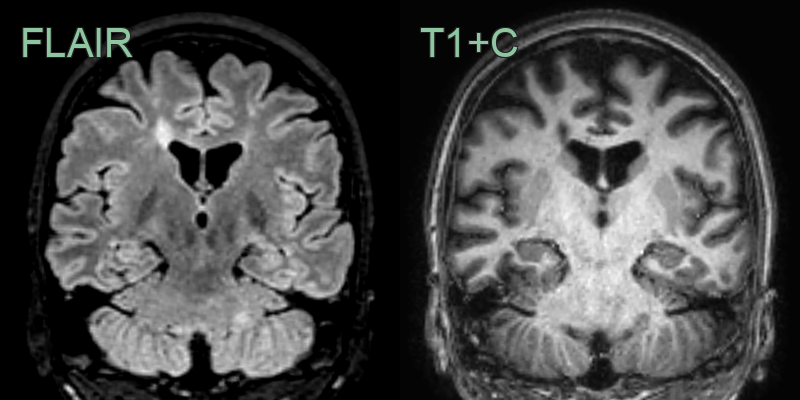

* 45-year-old patient with relapsing remitting multiple sclerosis showing lesions in the juxtacortical, periventricular, posterior fossa white matter, the corpus callosum and the cervical cord. * As there are lesions in more than one region set out in the MacDonald criteria, the imaging fulfils the criteria for dissemination in space. Dissemination in time would require either an enhancing lesion or a new lesion on a follow-up scan.